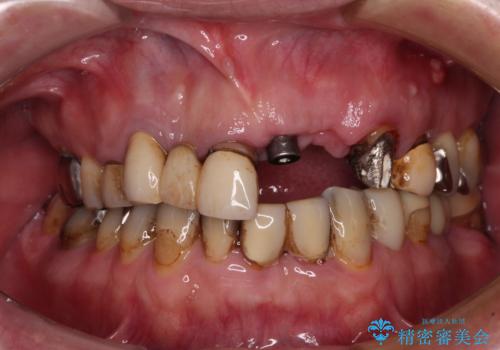

歯の破折による抜歯のため、歯槽骨の欠損が大きく、骨造成処置の併用が必要であり、骨造成が落ち着くまでに半年ほど時間を要することになります。

2本同時に抜去して一時的な入れ歯の使用を提案しましたが、極力固定式の仮歯を使用したいとのことで、半年に1本ずつ埋入することとし、トータルで1年強を要する治療計画となりました。

治療により前歯は非常に安定しましたが、インプラント部の両隣、特に反対側の前歯はクラウンのやり直しが必要な状態であったので、今後反対側の治療も実施していく予定です。